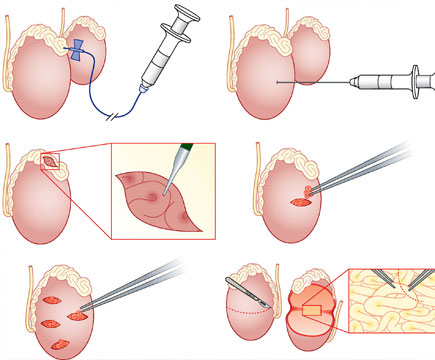

• Microsurgical Epididymis Sperm Aspiration

• Open fine needle aspiration

• Percutaneous Epididymis Sperm Aspiration

• Testicular Epididymal Sperm Extraction (TESE)

• Micro Dissection Testicular Sperm Extraction (TESE)

• Microsurgical Epididymal Sperm Aspiration is preferred as a Sperm Retrieval Method

• Under Local anesthesia, a small incision is made in the scrotum

• After, a micro puncture pipette quickly and very clearly punctures the Epididymal Tubule, then the sperm will be aspirated through the pipette

• After that, the sperm is examined under a microscope for viability, and the incision is closed with micro sutures

• This results in easier identification of sperm and processing for both fresh and frozen samples, as well as less damage to Epididymal Ductules

• These procedures may provide enough sperm for IVF (In Vitro Fertilization) and ICSI or Cryopreservation

• Open Fine Needle Aspiration is the Epididymis exposed and a ductule is directly punctured through the tunica, there is no any dissection

• Then using a 26-G needle for the purpose of aspiration

• Epididymal fluid is aspirated from the ductule

• After withdrawing the needle, the Epididymal fluid continues to flow out of the punctured ductule fluid and is aspirated from the Epididymal surface

• The ductular opening is not sutured

• Percutaneous Epididymal Sperm Aspiration is one of the best method used for men with Obstructive Azoospermia

• Percutaneous Epididymal Sperm Aspiration is the least invasive option and does not require any special surgical equipments

• Although this procedure used in men without dilated different epididymal tubules will often not provide enough sperms for Cryopreservation

• Percutaneous Epididymal Sperm Aspiration can provide enough sperm for Fresh-cycle In Vitro Fertilization (IVF) and Intra-Cytoplasmic Sperm Injection (ICSI)

• A small 30-GA needle is used in this aspiration and this needle is inserted percutaneous into the epididymis and its contents are aspirated

• If no sperms are found, the surgeon may elect to precede to a Microsurgical Epididymal Sperm Aspiration procedure or, more commonly Testicular Sperm Extraction

• A Testicular Biopsy or Testicular Epididymal Sperm Extraction is executed through an opening as a small scrotal incision

• TESE can be performed with or without the use of a Surgical microscope

• The Testicle is exposed and a Transverse incision is made in the anterior aspect of the Tunica Albuginea. Standard Open Testicular Sperm Extraction techniques may not find Spermatozoa in over half of men

• Patients usually Cryopreserve Sperm during this procedure for future In Vitro Fertilization (IVF) and Intra-Cytoplasmic Sperm Injection (ICSI)